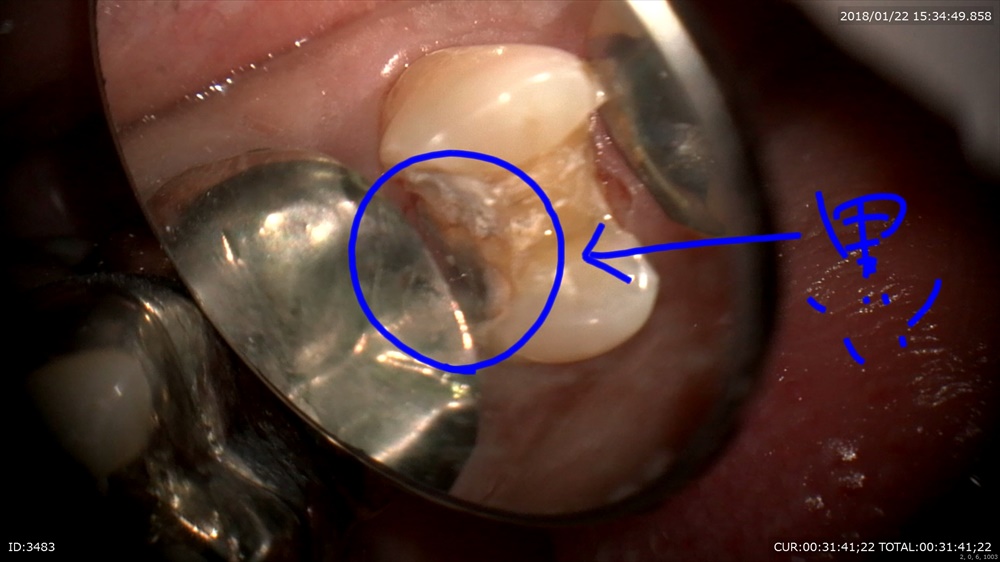

次はむし歯

銀歯むし歯の恐ろしさ。。。

銀歯が取れたで来院。歯科ドックで歯茎の中までむし歯と診断しました。

丁寧に。深い。歯茎の中まで。銀歯の恐ろしさ。。

ここで電気メス!(無痛)